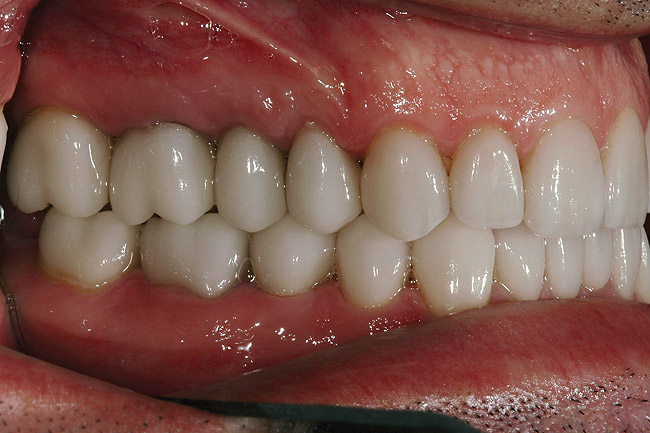

Figure 36   Retracted left postoperative view of the IPS e.max restorations.

Figure 36